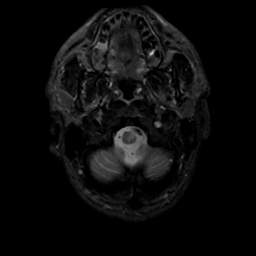

MR Study #3, February 24, 1991 -- Slice #3

[Home][Help][Clinical][Tour 1][Tour 2] Slice 3